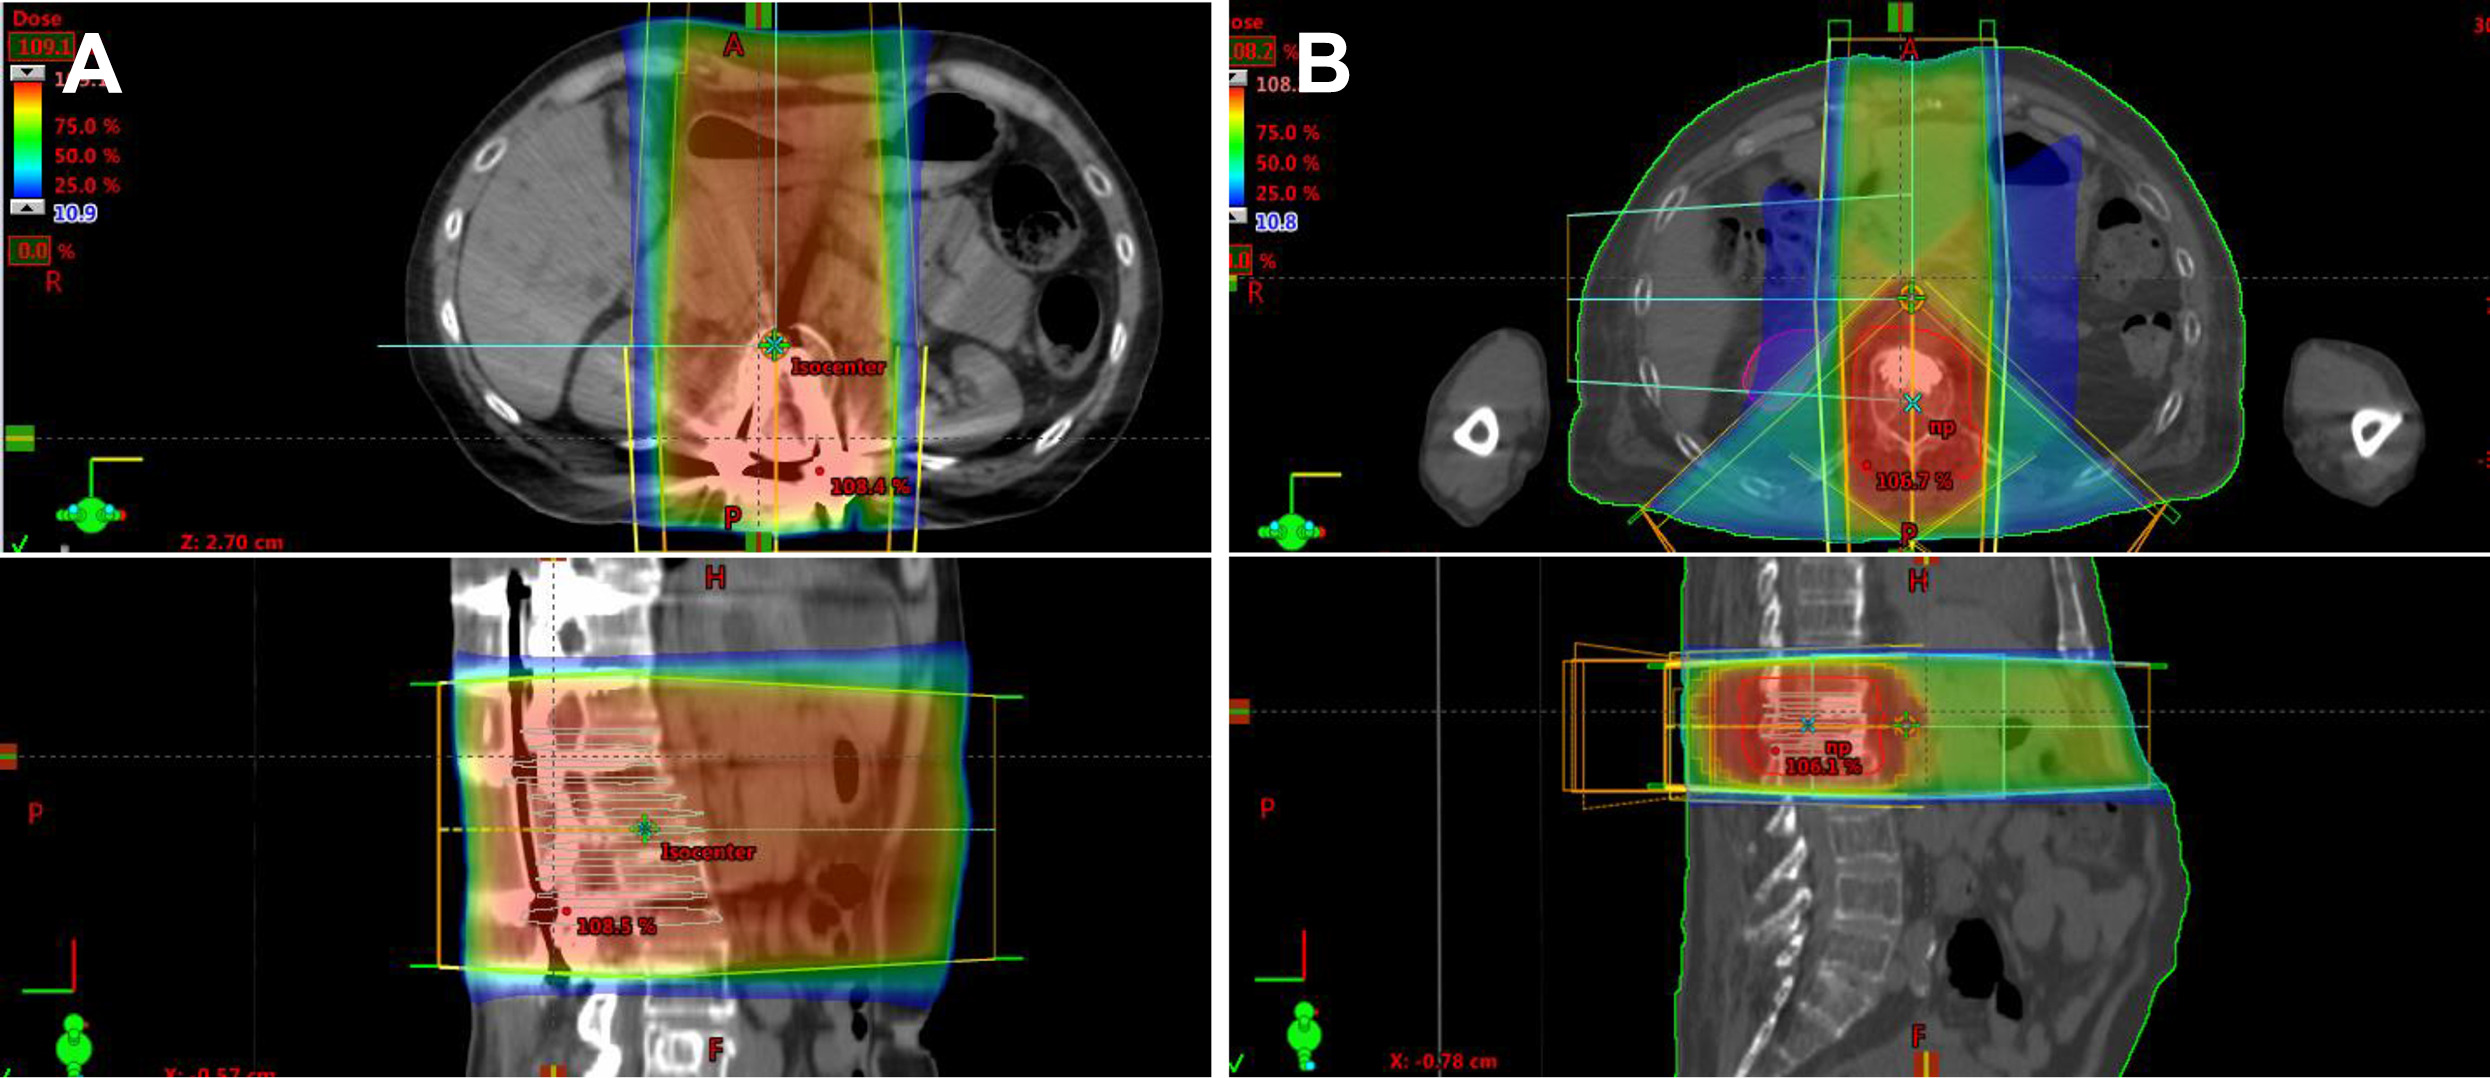

The dosimetrist is certified by the Medical Dosimetrists Certification Board and appreciates the radiation treatment process and equipment. They work closely with the medical physicist and radiation oncologist and ensure the accurate delivery of the prescribed dose of radiation while documenting pertinent information and verifying the mathematical accuracy of all calculations. They essentially map out the radiation delivery path using CT scans and MRIs to create a customized treatment plan for each patient. Using specialized computer software, they calculate the exact amount of radiation needed for each patient based on their tumor location and size, considering factors like beam angles and treatment fractionation.

Intensity-modulated Radiation Therapy, IMRT, allows the radiation dose to be shaped to the contours of the tumor, minimizing exposure to healthy tissue. This is achieved with the Multi-leaf Collimator, MLC, which is a computer-controlled device inside the head of the linear accelerator made up of many closely spaced, movable leaves that adjust independently to block parts of the beam. When active, the collimator moves organically, creating polygons that match the tumor’s profile even as the machine rotates.

Image Guided Radiation Therapy, IGRT, the standard of radiation treatment, involves taking high-quality images before each radiation therapy treatment session to increase the accuracy and precision of the radiation delivery. This ensures that any changes in the body or the tumor are accounted for.

Volumetric Modulated Arc Therapy, V-MAT, involves radiation delivery in a continuous 360-degree rotation around the patient, providing highly conformal dose distributions. This technique reduces treatment delivery time (in as little as 10 minutes), which improves targeting accuracy and patient comfort.